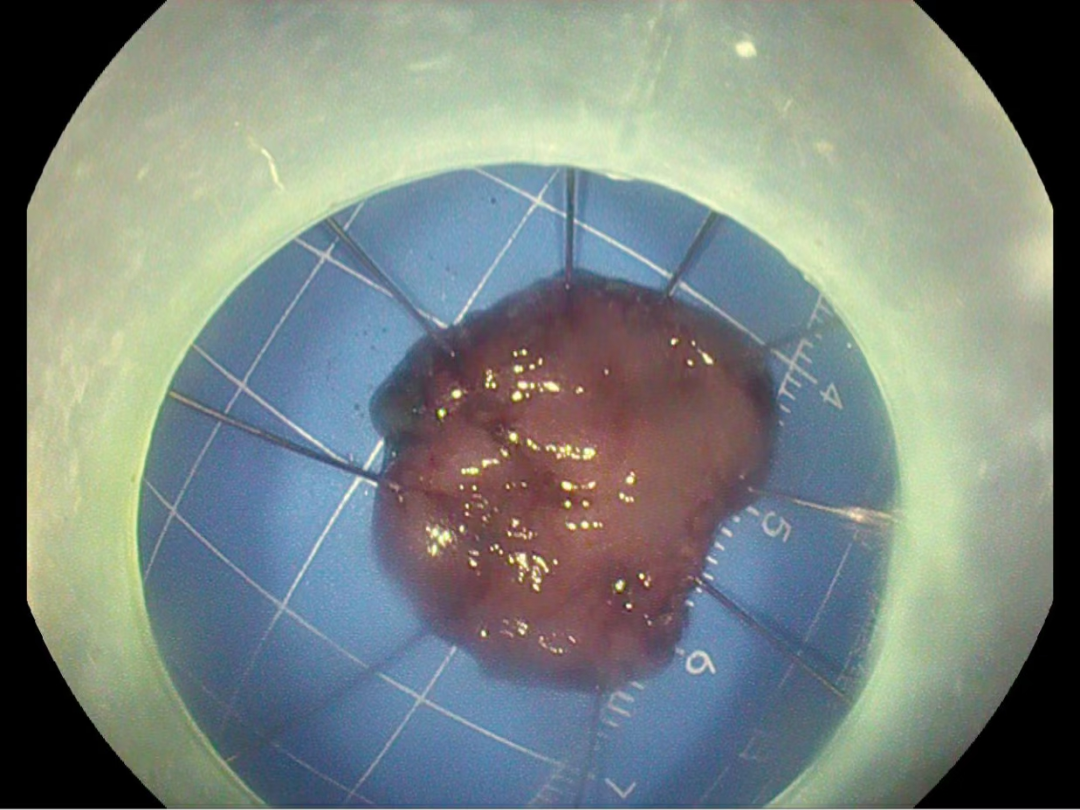

在蘇連明副主任醫師的帶領下,由多學(xué)科診療團隊爲李先生行氣管插管全麻下胃鏡下早期胃癌ESD術,在胃鏡下成(chéng)功將(jiāng)胃早癌病竈完整切除,術後(hòu)切除組織病理提示:胃早期癌變,切緣幹淨未見癌細胞浸潤,無需追加外科手術,胃鏡下已基本治療早期胃癌。對(duì)于這(zhè)樣(yàng)的結果,李先生激動地說(shuō):“感謝六院消化内科用先進(jìn)的技術幫助他解決了病痛,免除了外科開(kāi)刀的風險。”對(duì)于消化内科團隊的付出表示衷心的感謝,懷著(zhe)感恩且激動的心情順利出院。

▼術後(hòu)病理結果如下